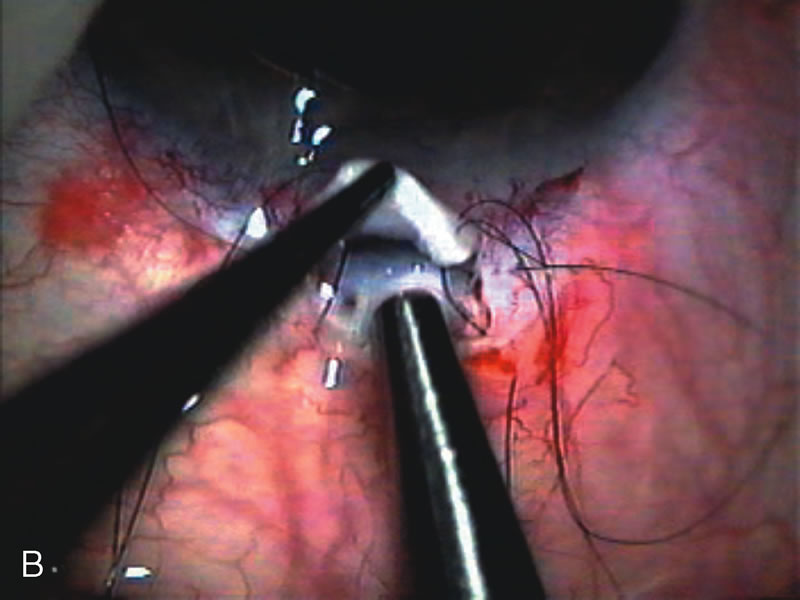

Nonpenetrating procedures as they exist today generally decrease postoperative complications but do not reduce IOP as successfully as trabeculectomy.140 The success rate also appears to be highly dependent on race, length of topical antiglaucoma therapy, and prior ocular surgery.141,142 Deep sclerectomy combined with phacoemulsification results in an IOP reduction similar to phacotrabeculectomy at one year with comparable visual outcome.143 Phacoviscocanalostomy lowers IOP by approximately 33%144 through either a one- or two-site approach145 (Fig. 4). Nonpenetrating procedures are in evolution, and their place in long-term glaucoma care is still unclear.

Fig. 4. Viscocanalostomy with deep sclerectomy and phacoemulsification. Nonpenetrating filtration procedures (NPFS) may be combined with phacoemulsification. Patients with mild disc damage and a history of limited topical drug therapy are the best candidates. Patients who require an IOP in the low teens are not good candidates for NPFS. By definition, NPFS is designed to lower IOP without penetrating into the anterior chamber, thereby avoiding the complications associated with trabeculectomy. Viscocanalostomy is intended to allow aqueous to percolate through a trabeculodescemetic membrane into a subscleral cavern created by the deep sclerectomy. The aqueous diffuses from the cavern into the dilated ostia of Schlemm's canal and into the episcleral venous plexus. A. Fashion a uniform 300-micron superficial scleral flap 1 mm into clear cornea. B. Construct a second 600-micron deep flap that facilitates the unroofing of Schlemm's canal, seen as the darker area. C. Use viscoelastic to dilate the ostia of Schlemm's canal. The major problem with viscocanalostomy is the eventual closure of the ostium decreasing flow to the episcleral plexus. D. Dissect the deep flap anteriorly into clear cornea creating the trabeculodescemetic membrane. This membrane is clearly seen between the scleral spur and the bend of the deep flap. The integrity of this membrane ensures the nonpenetrating portion of the surgery. Another problem with NPFS is the eventual fibrosis of this initially transparent membrane requiring goniopuncture. E. Deep sclerectomy gets its name from removal of the deep flap. Removal of this flap creates the potential subscleral space for accumulation of aqueous before it enters Schlemm's canal and exits the episcleral venous plexus. After removal of the deep flap, the superficial flap is sutured into place and conjunctiva closed. Approximately half of these procedures develop a shallow bleb.